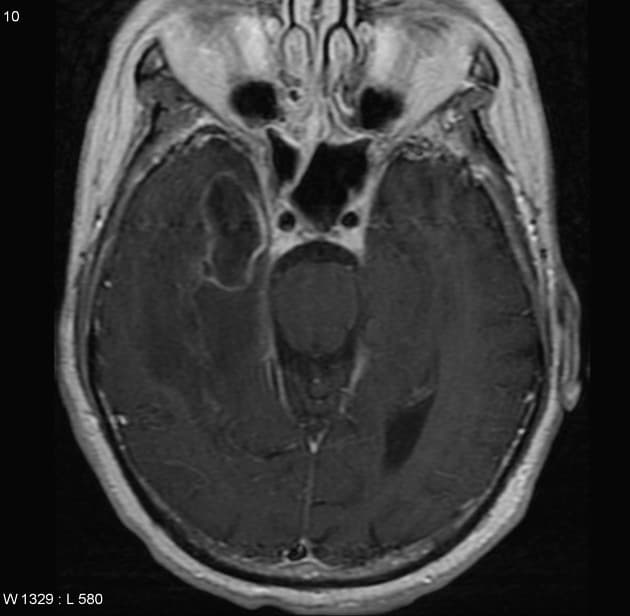

U nguyên bào thần kinh đệm đa ổ - IDH dạng hoang dại

Hai khối trong trục, bắt thuốc viền (rim-enhancing), khu trú ở vùng trán hai bên, nằm tại vùng giao giữa chất xám và chất trắng.

Phù vận mạch (vasogenic edema) xung quanh, có hiệu ứng khối nhẹ tại các rãnh thùy trán trái, gây xóa (effacement) các rãnh não.

Không thấy lệch đường giữa (midline shift) hay thoát vị não (brain herniation).

Không thấy xuất huyết nội sọ (intracranial hemorrhage).

Hai khối trong trục: một ở thùy trán (frontal lobe) trái và một ở thùy trán phải.

- Cả hai đều có viền tăng quang, viền tín hiệu T2 trung gian, trung tâm không đồng nhất (heterogeneous) trên T2, và tín hiệu T1 thấp đến trung gian.

- Cả hai đều có hiệu ứng nhiễu từ (susceptibility artifact) trên SWI, tương ứng với sản phẩm máu trên ảnh pha (phase imaging).

- Mỗi khối được bao quanh bởi vùng tăng tín hiệu trên T2/FLAIR, nhưng không liên tục giữa hai khối.

Nốt nhỏ tăng quang ở phía sau rảnh Sylvius (sylvian fissure) phải.

Hai khối trong trục tăng quang ở vùng ngoại vi và một vùng tăng quang dạng nốt, hình ảnh này nghi ngờ nhiều nhất là di căn (metastases). Các khối chứa sản phẩm máu, và do không tìm thấy khối u nguyên phát trên CT ngực-bụng-chậu (CT CAP), cần cân nhắc ung thư hắc tố ác tính (malignant melanoma) (mặc dù không có tăng tín hiệu nội tại trên T1).

Các khối trong trục bắt thuốc dạng viền (ring-enhancing) có phổ chẩn đoán phân biệt rộng và đã được biết rõ. Ở nhóm tuổi và lâm sàng như trường hợp này, di căn não (cerebral metastases) là nguyên nhân phổ biến nhất, và đây là chẩn đoán nghi ngờ cả về hình ảnh học lẫn lâm sàng. Kết quả sinh thiết tức thời (frozen section) trong mổ cũng được báo cáo là tổn thương di căn; tuy nhiên, sinh thiết mô học chính thức (formal histopathology) cho thấy cả hai tổn thương đều là u nguyên bào thần kinh đệm (glioblastoma), IDH dạng hoang dại (IDH-wildtype). Do không có vùng tăng tín hiệu T2/FLAIR liên tục nối liền hai tổn thương, nên được xem là u nguyên bào thần kinh đệm đa ổ (multicentric glioblastoma) – một dạng hiếm gặp.

U nguyên bào thần kinh đệm đa ổ - IDH dạng hoang dại (Multicentric glioblastoma - IDH-wildtype)

- "U nguyên bào thần kinh đệm đa ổ được định nghĩa là có nhiều ổ tổn thương không liên tục, không nối với nhau qua các bó sợi chất trắng."

- "Việc không có vùng tăng tín hiệu T2/FLAIR nối liền các tổn thương giúp phân biệt dạng đa ổ với dạng đa ổ lan theo bó trắng."

- "U nguyên bào thần kinh đệm IDH dạng hoang dại là dạng phân tử phổ biến nhất và ác tính nhất, thường gặp ở người lớn tuổi."